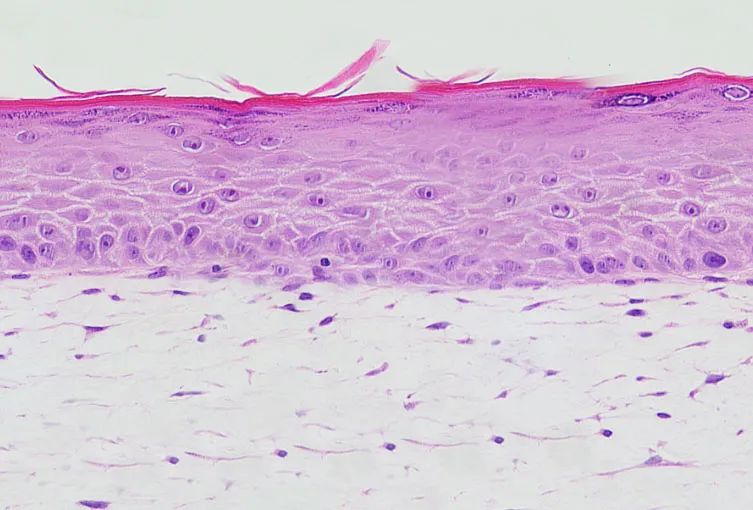

其中EpiKutis 是由中国人皮肤组织分离出的角质形成细胞,在特定的培养环境下生成的活性组织(属于组织工程技术)。它与正常人体表皮高度类似,是具有典型的基底层、棘层、颗粒层及角质层的表皮复层化结构。

图:EpiKutis 表皮模型,图源博溪生物官网

EpiKutis 是目前国内首款实现产业化生产的皮肤测试模型,也是皮肤生物学研究和化妆品体外功效性评价的一个有效工具。